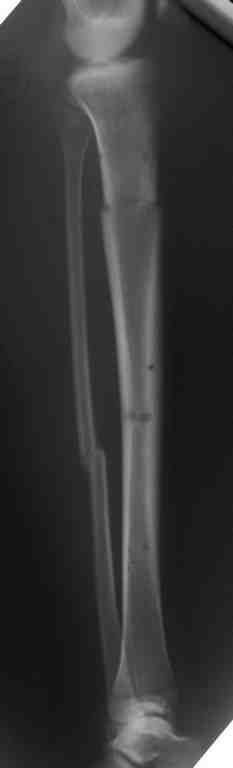

Выше представлены рентгенограммы открытого оскольчатого перелома нижней трети голени X-rays of Compound Comminuted # Distal/3 Lt Tibia

Операционные снимки перед и после наложения аппарата Илизарова In operation room before and after Ilizarov apparatus has been applied

Послеоперационные рентгенограммы Postoperative X-rays

В нижнем ряду представлены рентгенограммы после окончательной репозиции. And final reduction after Hexapod program has been finished